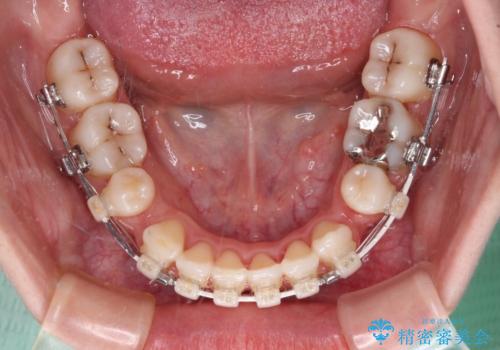

上下前歯が非接触である開咬は、インビザラインによる治療がお勧めではありますが、非抜歯矯正か抜歯矯正か悩む口元であり、途中抜歯矯正に切り替えたときに対応しやすいよう、ワイヤー装置にて治療を行うこととしました。

舌の突出癖の影響もあり、非抜歯矯正で治療開始したものの口元が突出し、唇が閉じにくくなってしまったため、途中で第一小臼歯4本を抜歯ししました。